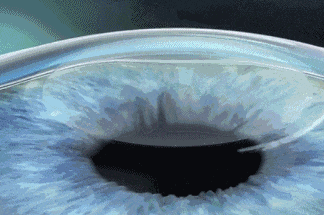

我们通常说的全飞秒手术,标准的名称是:微小切口基质透镜切除术,手术的基本原理其实和传统的角膜屈光手术类似,是把角膜中间区变薄一些,改变角膜的曲率,相当于在角膜上“制作一副镜片”,以达到矫正近视的目的。

全飞秒手术的优势是不需要制作角膜瓣,而且切口更小、更舒适、恢复更快!

而如今的新全飞秒 SMILE Pro技术,在这一成熟原理基础上进一步升级:全程采用飞秒激光完成,无需制作角膜瓣,仅通过一个2-4毫米的微小切口即可取出透镜。相比以往,新全飞不仅切口更小、创伤更轻,还显著提升了术后舒适度,恢复更快、视觉质量更优,是当前近视矫正领域更安全、更精准、更舒适的前沿选择。